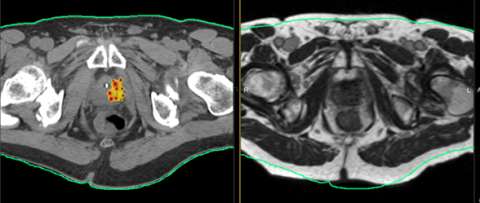

Above is another example of a focal salvage case of a patient who had a local failure within a cold spot of a LDR seed implant. Again only a portion of the gland was treated for this patient.